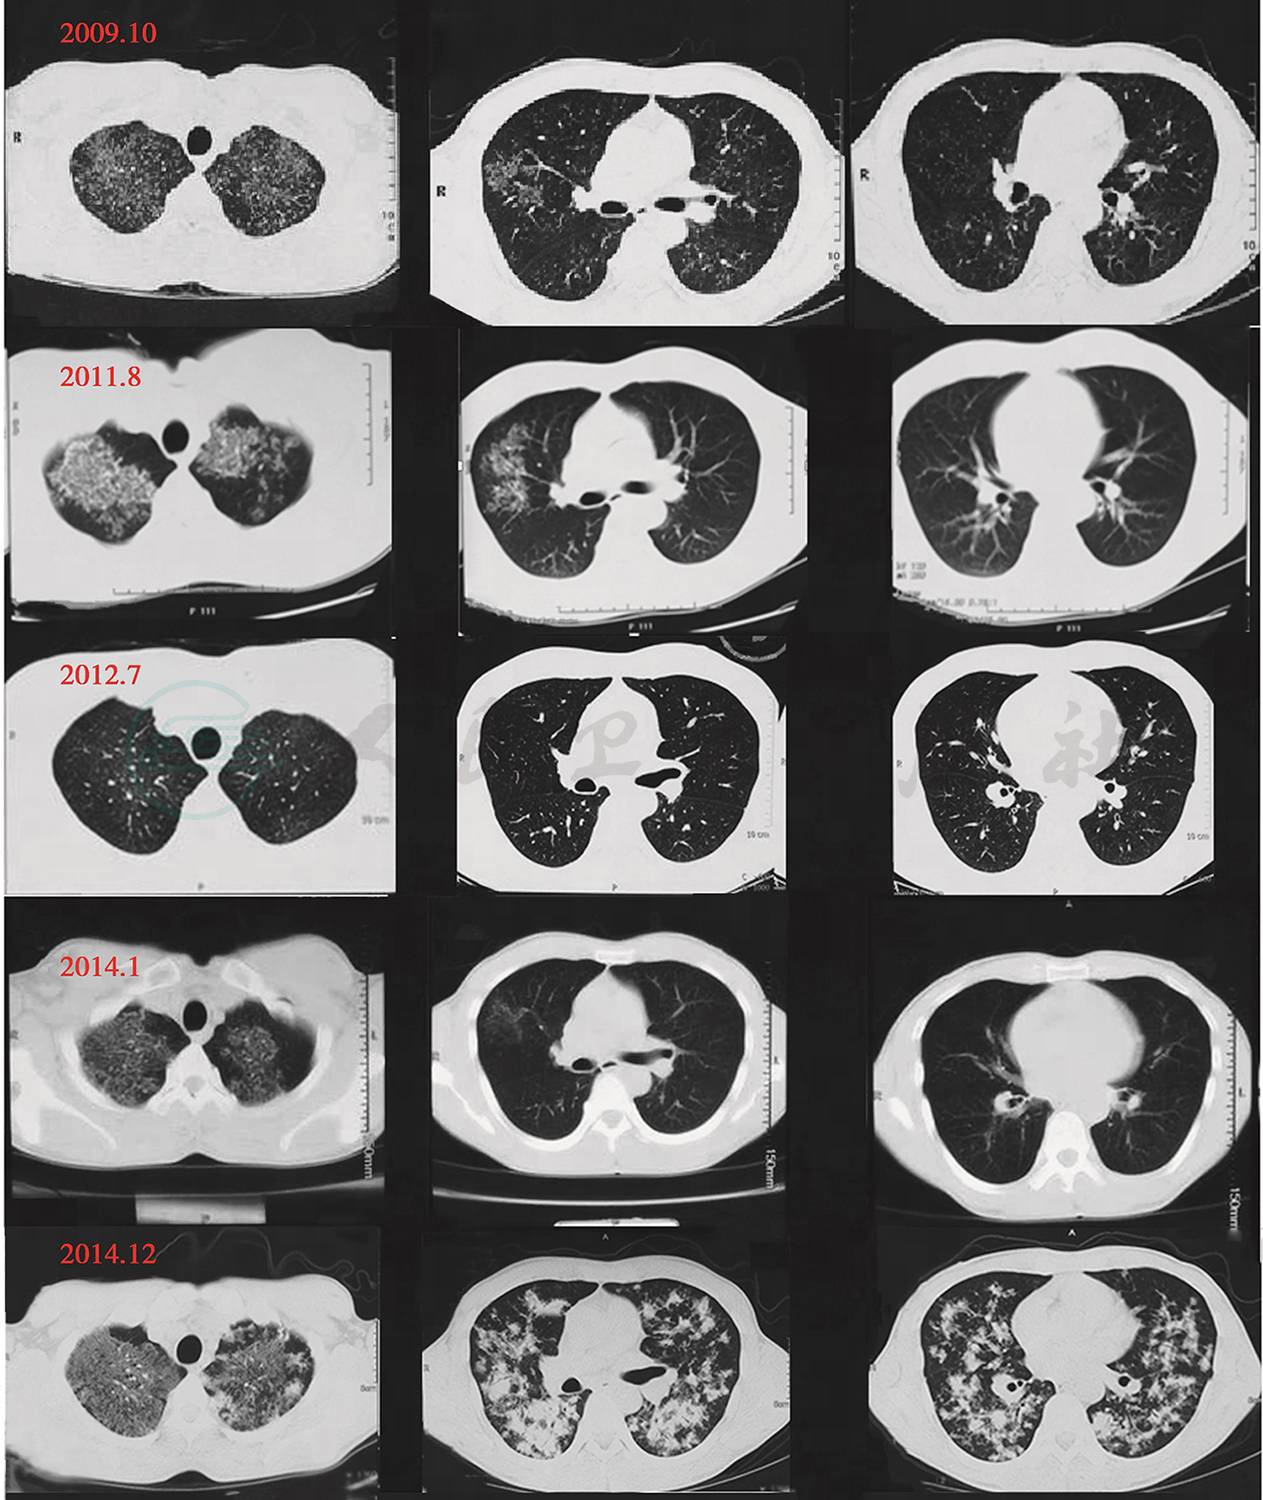

患者于2009年受凉后出现阵发性咳嗽,为干咳,晨起、进食时加重,约持续1min,每天4~5次,无呼吸困难、胸痛、咳痰、咯血、乏力等症状。于当地医院诊断为肺结核予以抗结核四联+护肝规律治疗7个月,因症状无缓解入住当地医院15天予以抗结核治疗(具体用药不详),症状未有明显缓解,于2011年11月始以中药抗结核治疗4个月,并于2012年7月复查CT(图1)示胸部病变较前好转,原双上肺斑片状、片状密度增高影基本吸收,双上肺可见散在小结节状密度增高影。患者自觉症状无明显缓解或加重,咳嗽症状反复,为求进一步诊治于2014年1月来我院,胸部CT(图1)结果及临床考虑诊断为肺泡蛋白沉着症,因患者自身因素未进一步治疗。2014年10月始患者无明显诱因出现活动后气促,吸气期及呼气期均感呼吸费力、呼吸频率增快、深度变浅,伴胸痛、乏力、盗汗。2014年12月初出现咳痰,为白色黏痰,多发生在夜间。咳嗽持续时间及频率均增加。为求进一步诊治来我院复查胸部CT(图1)示双上肺病变密度增高较前增大,双肺多发结节状密度增高影较前增多,纵隔多发淋巴结增大。于2014年12月15日入住我科,患者自起病以来,精神食欲可,睡眠可,小便较少,大便正常,2个月体重下降约5kg。

图1 入院前CT

(包括2009年10月、2011年8月、2012年7月、2014年1月、2014年12月)